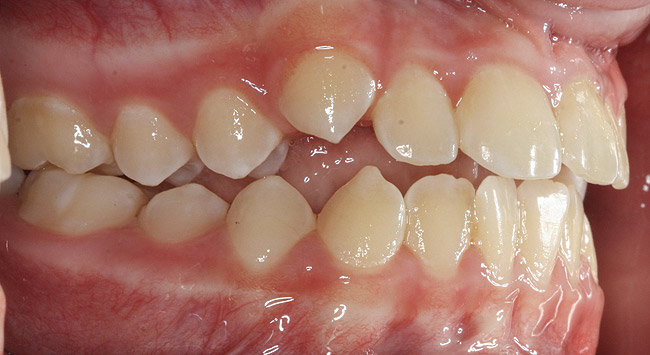

The point of obstruction tends to determine the type of skeletal impact. Nasal obstruction from enlarged turbinates, blocked ostium maxillare, deviated septum, or nasal valve stenosis creates Angle occlusions of Class I, II, and III equally (Figure 8). The maxilla in these cases is positioned posteriorly and the mandible is posterior-inferior. The facial type is most commonly dolicocephalic. Blockage of the airway predominately by the adenoids will create growth patterns that yield mostly Class II occlusions and anterior open bite with both jaws located posterior-inferiorly. Facial type is again dolicocephalic with the typical long-thin “adenoidal” face49 (Figure 9 through Figure 12). If the tonsillar tissue is responsible for the airway obstruction, the tongue will have an abnormal resting posture. Class III occlusions will be more common with the maxilla normal or posterior placed (Figure 13 through 15). The tongue may direct the mandible anteriorly or, because the tongue is not in the roof of the mouth driving A point anterior, the maxilla will become bimaxillary retrusive.50 In some cases, the anterior posture of the tongue will create an open bite. This is incorrectly referred to as a tongue thrust. The impact from a thrust does not alter the tooth position. Long-term, low forces cause tooth movement. The posture of the tongue against or between the anterior teeth due to the excessive tonsillar size creates the open bite (Figure 16 and Figure 17). Facial types in this group are more brachyfacial. Lastly, if the airway is blocked through a combination of factors, the Angle classification will be either Class II or III. The maxilla will be in a normal location and the mandible will be the affected arch (Figure 18). These craniofacial changes are not restricted to OSA; all SDB will create unique alterations depending on the patient compensation. Children with UARS have been reported to display high, narrow palates, dolicofacial form, and a Class II malocclusion, indicative of largely adenoidal blockage.51

(13.) Seven-year-old brachyfacial child with high body mass index (Case courtesy of James Awbrey, DMD).

(16.) Tongues with poor tone and posture may move the teeth over time and open the bite (Case courtesy of James Awbrey, DMD).